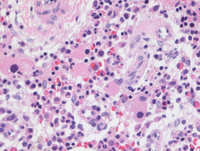

Aspirate smears

On the aspirate smears erythroid maturation is progressive with some atypia/nuclear irregularity and megaloblastoid change. There is no vacuolation in the erythroid precursors (as might be seen with copper deficiency). Myeloid maturation is left shifted with very occasional neutrophils with abnormal chromatin clumping. Lymphoid cells are not significantly increased.